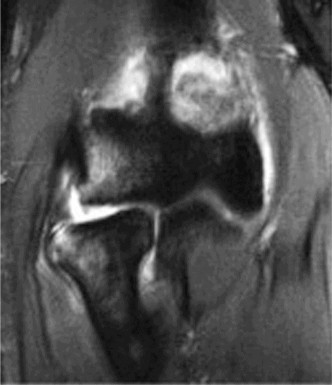

The correct answer is (A). In a young patient, the most likely injury associated with a glenohumeral dislocation is a labral tear (see Fig. 2–31). In an older patient, >40 years old, a rotator cuff tear is more likely. Other possible associated injuries include:

Figure 2–31 MRA demonstrating an anterior labral tear.

Bony Bankart Hill–Sachs

Humeral avulsion of the glenohumeral ligament (HAGL) Glenoid labral articular defect (GLAD)

Anterior labral periosteal sleeve avulsion (ALPSA) Fracture

Axillary nerve injury (estimated to occur 5% of the time)

These all are less common than a labral tear. Each of these injuries need to be identified and treated appropriately at the time of surgery to ensure a satisfactory outcome.